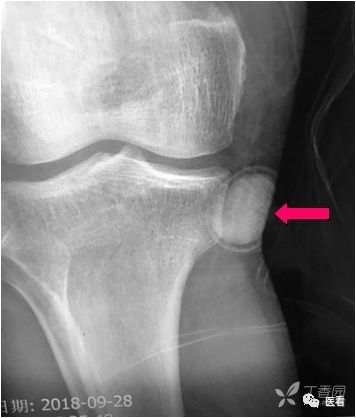

7 受检者体内、体表高密度组织结构形成的伪影

鸡冠 (红箭)所致放 射伪影 (黄箭)